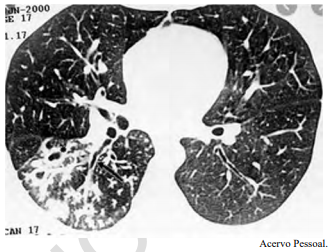

Um adolescente de 17 anos de idade procura atendimento em função de tosse vespertina, febre e hemoptise em pequena quantidade. Refere sudorese noturna e perda de peso. A tomografia de tórax apresenta nódulos centrolobulares com padrão de árvore em brotamento, além de pequenas cavitações espessas e de paredes irregulares, bem como brônquios espessados em segmento posterior do lobo inferior direito, conforme a imagem a seguir.

Tendo em vista esse caso clínico, a imagem apresentada e os conhecimentos médicos correlatos, julgue o item a seguir.

O paciente tem como principais complicações possíveis da doença hemoptise, atelectasia, empiema e formação de bronquiectasias.